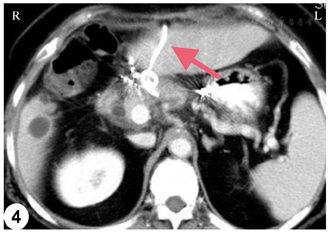

患者来本院寻求手术治疗,遂决定行开腹手术。开腹探查发现胰颈部可见一质硬实性肿块,向胰腺上缘突出。结合术中情况,患者无胃癌复发迹象,肿瘤与肝总动脉、肝固有动脉及胃十二指肠动脉关系密切,考虑难以行手术切除,因此决定行术中超声引导下RFA治疗。Kocher钳游离胰头和十二指肠。患者曾接受过根治性胃切除术,因此游离胰腺上缘的膜性粘连。分离肝十二指肠韧带右缘,冷湿纱布覆盖周围组织器官,充分暴露胰头和胰颈。采用Cool-tip™ RFA系统以及冷循环电极(17-gauge)(图3A)。然后在术中超声引导下将射频电极精确地插入肿瘤内(图3B)。启动后设置手动功率输出,从40 W开始,随后将功率以10 W/min速率增加,以90 W的最大功率进行肿瘤消融,共消融3点次(每次6~10 min)。于胰体及winslow孔置管引流(图4)。术后予以抗感染,抑酸,抑制胰腺分泌对症支持治疗。